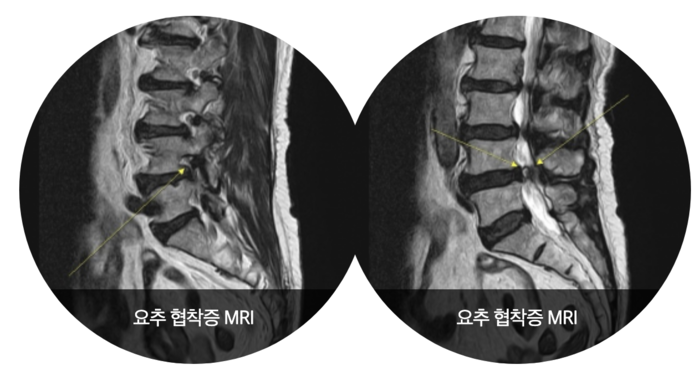

- 영상 검사: X선, MRI, CT와 같은 검사로 척추의 구조적 문제를 확인합니다. 이를 통해 신경이 얼마나 압박받고 있는지에 대한 정보를 제공합니다.